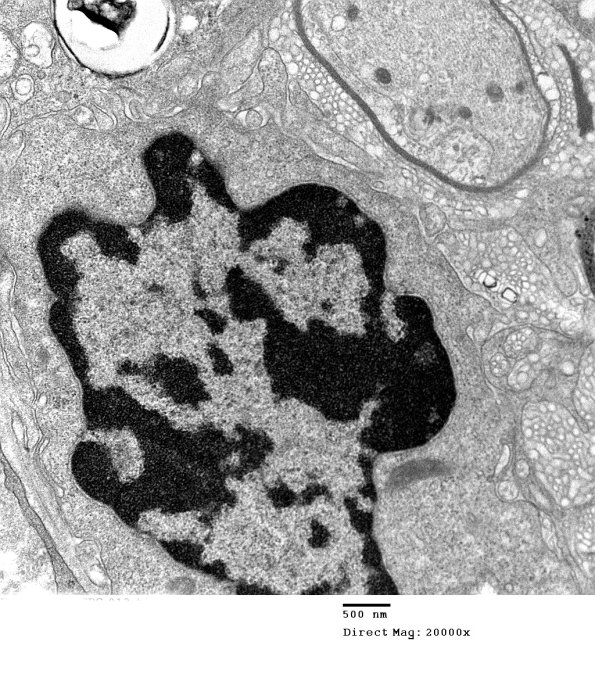

Is this demyelination or remyelination? The higher magnification image shows vesicular myelin in contact with the thin remaining myelin most consistent with late demyelination. (electron micrograph)